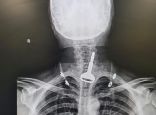

القنفذة.. تدخّل جراحي يُنقذ حياة مريض ابتلع مفتاح سيارته

نجح فريق طبي بمحافظة القنفذة في استخراج مفتاح سيارة من الجهاز التنفسي لمريض أربعيني كاد أن يودي بحياته، في عملية استغرقت 15 دقيقة عن طريق المنظار.

وأكدت "الصحة" في القنفذة أن ..